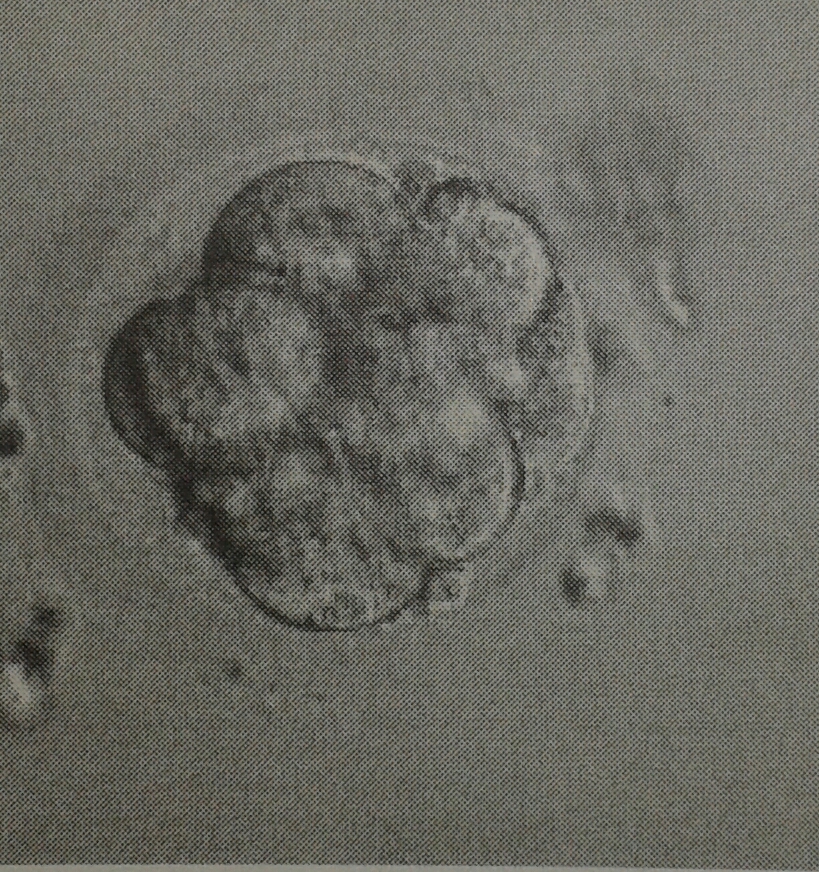

Anbei auch mal Bilder unserer Beiden .. ich hoffe so sehr sie sind noch bei mir *dd*

Dateianhänge

20140620_175734-1-1.jpg

20140620_175728-1.jpg

05.05.14 PU 9 Eizellen, davon 8 reife EZ

06.05.14 8 EZ befruchtet ... 100% wow

09.05.14 ET von einem 8 Zeller und einem Morula ...